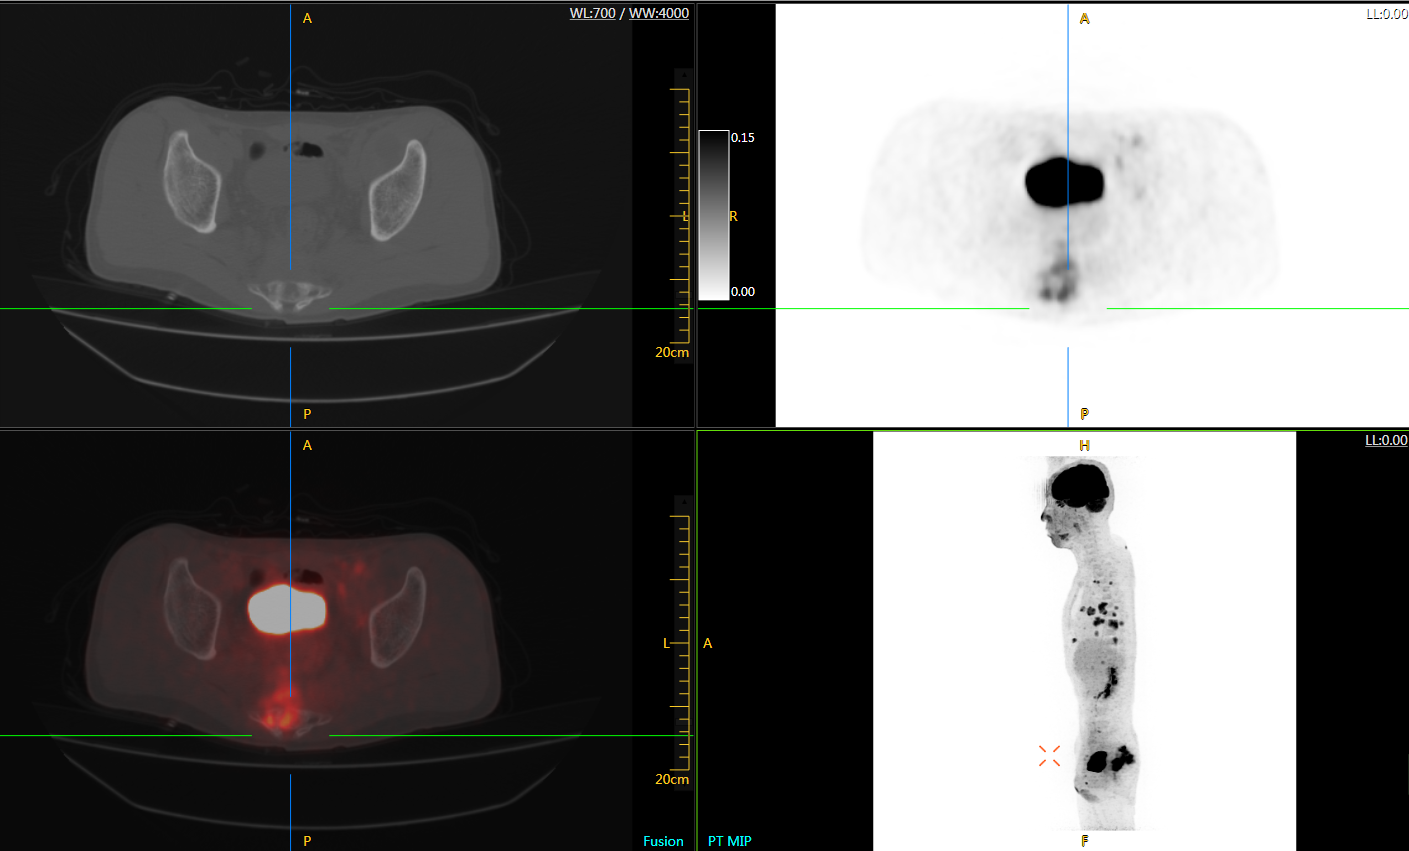

肺癌轉(zhuǎn)移及復(fù)發(fā)

患者男性,66歲,七年前發(fā)現(xiàn)右肺肺癌,其間手術(shù)兩次,共切除兩個肺葉,復(fù)查;

診斷意見,回腸轉(zhuǎn)移,右肺殘留部復(fù)發(fā)